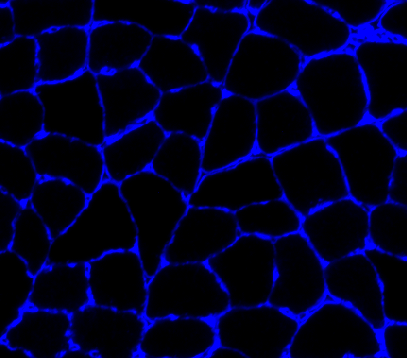

PoWer_3_Gastroc_10x_blue_cropped_small.pngstored in..\demos\example_A\raw_image - results to be written to

reading in the input image file

converting it to gray-scale

- saturating the image

enhancing the cell edges using a Frangi filter